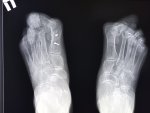

И снова здравствуйте! Сегодня! В этом тредике! Мы будем с вами общатся и играть в доктора! Я буду вам постировать фоточки, а вы угадывать пиздецомы! Я все еще нихуя не успеваю, пытаюсь описать за 25 число, сегодня задержусь наверное после работы опять пытаясь нагнать нагрузку :-(